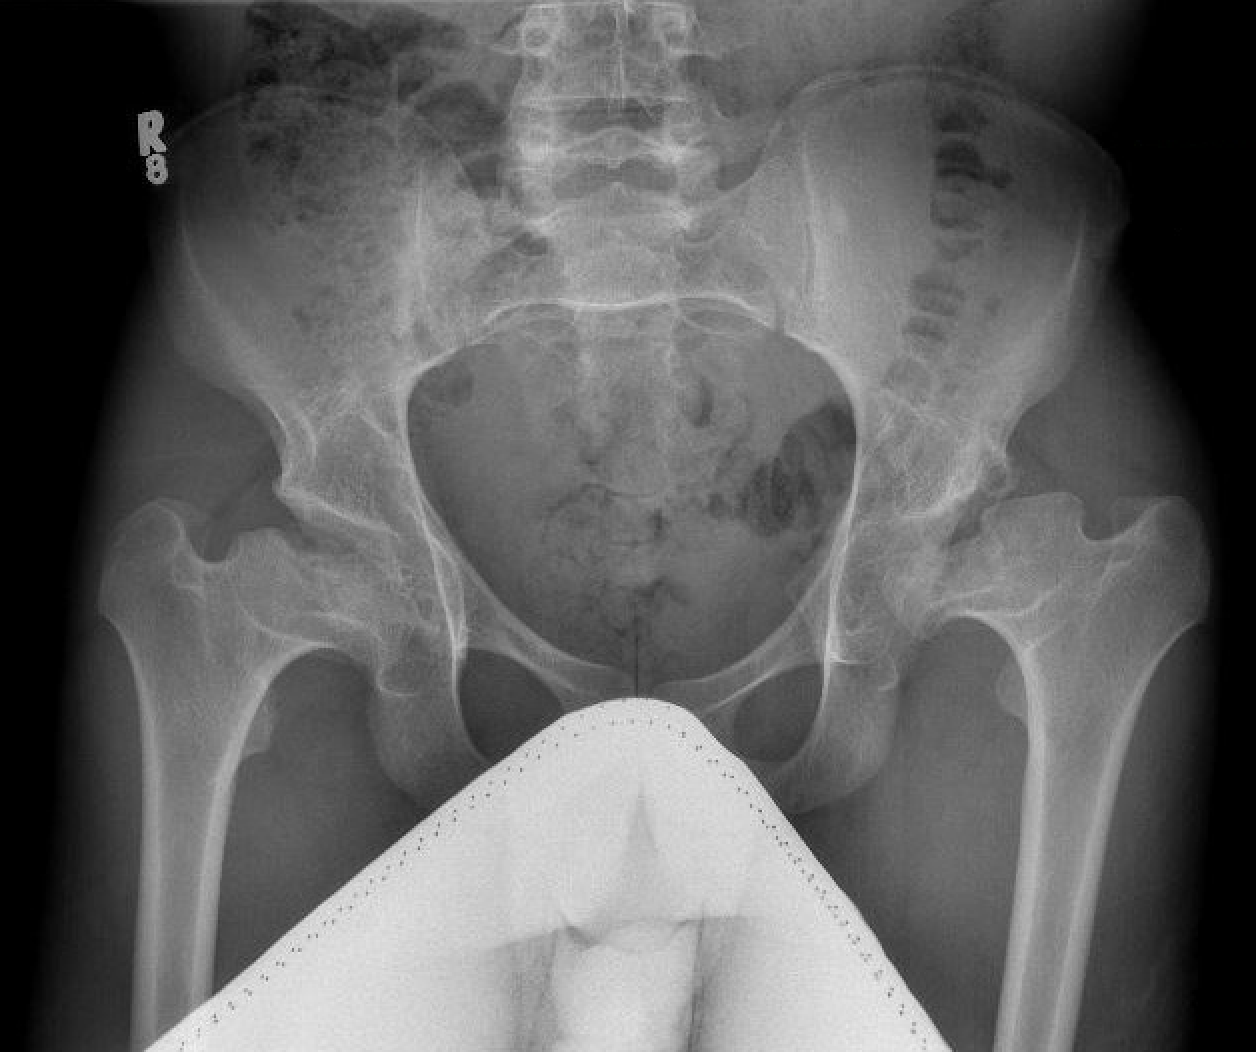

Issues

| Femur | Acetabulum | Leg Length Discrepancy | Abductors |

|---|---|---|---|

|

Multiplanar deformity |

Element dysplasia | 2 - 4 cm | Shortened |

| Worsened by previous surgery | May need trochanteric slide | ||

| Risk of intra-operative fracture | |||

| May require osteotomy |

Shallow acetabulum